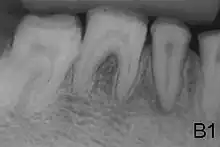

X-ray showing lack of enamel opacity and a pathological loss of enamel in patient with amelogenesis imperfecta